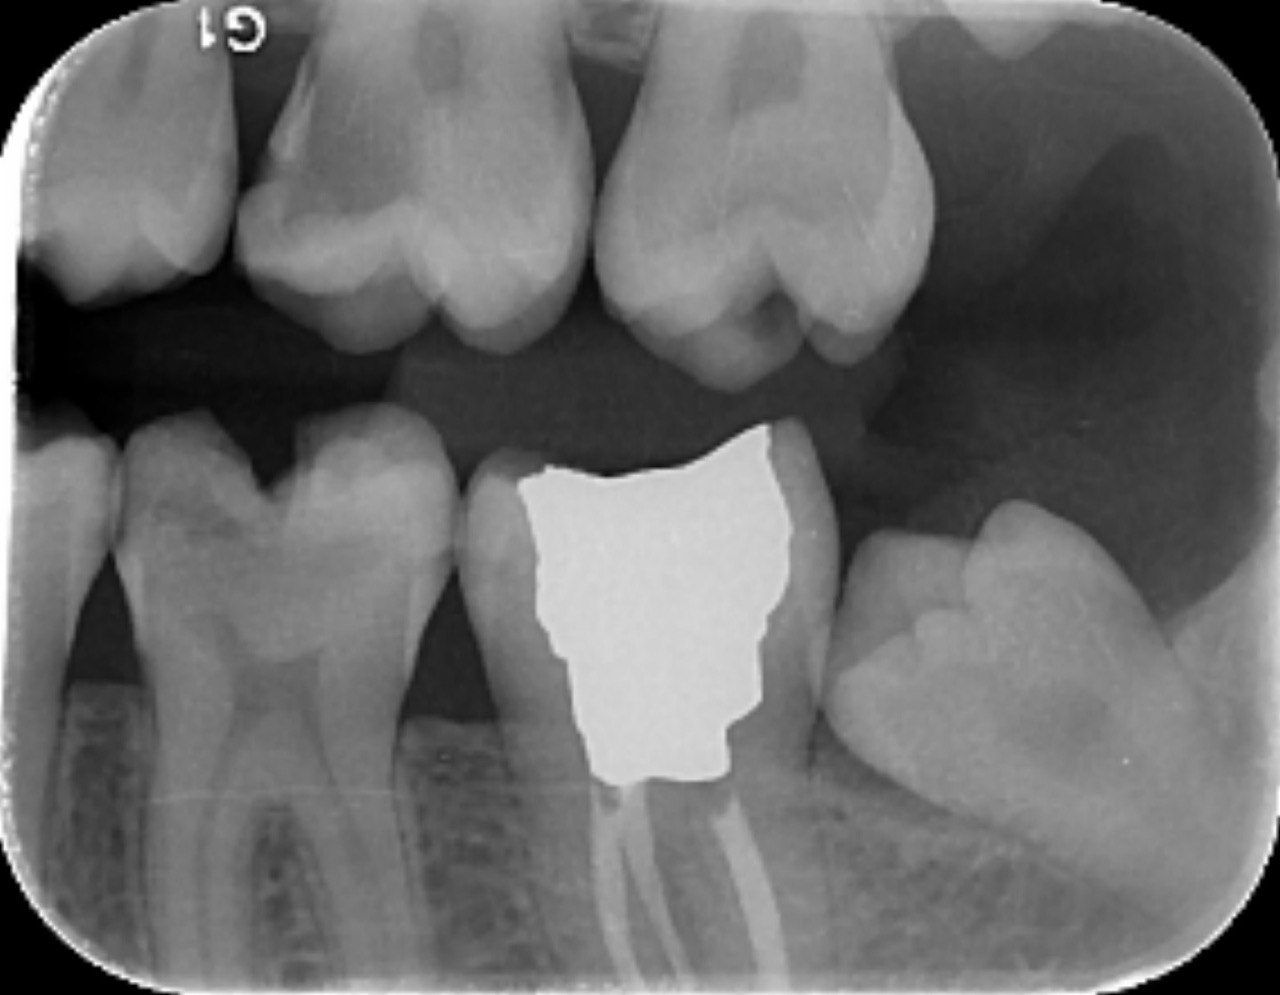

32. Which surfaces needs restoration?

38. Which surfaces shows recurrent caries?

40. Which surfaces shows recurrent caries?

42. Which surfaces shows recurrent caries?

43. Which surface shows recurrent caries?

45. Which surface shows recurrent caries?

46. Which teeth shows recurrent caries?

47. Which surface(s) shows recurrent caries?

50. Which surface(s) shows recurrent caries?